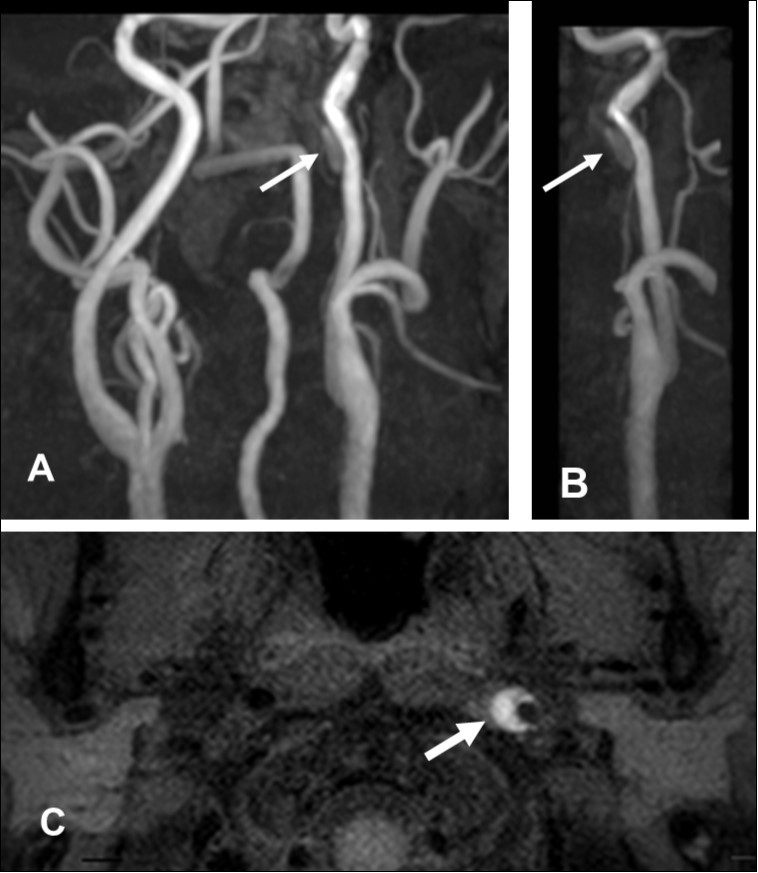

This 43-year-old Japanese male presented with right hand dysesthesia. He has not recognized his neck pain and Horner’s syndrome( oculosympathetic palsy). Magnetic resonance imaging(MRI) performed on a 3T TX scanner (Philips Achieva, The Netherlands) demonstrated dissection of the left cervical carotid artery (CCA; Figure 1A,1B ); no ischemic area was detected in the left cerebral brain. Axial section views of the CCA segment revealed a typical crescent hematoma; a bright, hyper-intense circle representing the narrowed arterial lumen was visualized. A T1-volumetric isotropic turbo spin echo acquisition (VISTA) sequence resulted in the diagnosis of dissection of the CS-ICA (Figure 1C). He had no conventional stroke risk factors such as hypertension, diabetes, hyperlipidemia, a history of cardiac valvular disease, arterial fibrillation, or features of inherited connective tissue disorder. Also absent was a history of arterial trauma and we were unable to identify any etiological factor(s). One week later he developed Gerstman symptoms; border zone ischemia was observed in the left cerebrum (Figure 2-Ic). He was admitted and the administration of antiplatelet agents was started. The left middle cerebral artery (MCA) was supplied via antegrade circulation (Figure 2-Ib) and an increase in the flow-void intensity was noted (compare Figure 1C with Figure 2-Ia). MRI studies acquired one week later revealed spreading of the ischemic area to beyond the watershed zone between the left anterior cerebral artery (ACA) and the MCA, and the MCA and the posterior cerebral artery (PCA) (Figure 2-IIc). The area of dissection had spread from the ICA bifurcation to the top of the ICA. The blood supply to the left MCA territory derived from the circle of Willis (Figure 2-IIb). The flow-void intensity had increased further (compare Figure 2-Ia with Figure 2-IIa). Two weeks after his admission he suddenly experienced complete right-sided hemiparesis with motor aphasia. MRI performed within 45 min demonstrated diffuse ischemia in the left MCA territory (Figure 2-IIIc), the left A1 segment could not be visualized. The left MCA and its A1 segment were completely occluded (Figure 2- IIIb). The flow-void intensity indicated complete occlusion of the true lumen (Figure 2-IIIa). He underwent emergency left superficial temporal artery (STA)-MCA bypass surgery within 6 hours; double anastomosis was successful. External decompression was performed to prevent neurological deterioration due to severe brain swelling. An intensive rehabilitation has been continued for him after operation. His functional independence measure (FIM) score recorded over the course of 4 months showed remarkable improvement ( Figure 3) as did the standard language test for aphasia.

Figure 1.First hospitalization. A. Maximum intensity projection ( MIP )image of arteries in the cervical segment. B. Magnetic resonance angiography of the left carotid artery. C. T1 VISTA sequence. Note the flow void reflective of the narrowed lumen next to intramural hematoma (hyperintense crescent)